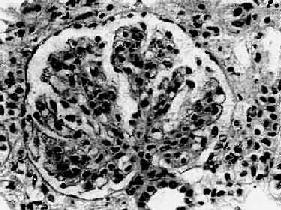

四、弥漫性膜性增生性肾小球肾炎弥漫性膜性增生性肾小球肾炎(diffuse membranoproliferative glomerulonephritis)又称系膜毛细血管性肾小球肾炎(mesangiocapillary glomerulonephritis),其病变特点为弥漫性肾小球毛细血管壁增厚和系膜增生。各种年龄都可发病,但多见于青年和中年人。起病缓慢,是一种慢性进行性疾病。早期症状不明显,临床症状表现不一,常有血尿、蛋白尿。约半数起病时即表现为肾病综合征,并常有高血压和肾功能不全。有些病人的血清补体降低,故又称为低补体血症性肾小球肾炎(hypocomplementemic glomerulonephritis)。 【病理变化】 肾小球系膜细胞和基质增生。系膜区增宽,其间常有数量不等的中性粒细胞浸润。增生的系膜组织逐渐向周围毛细血管伸展,侵入毛细血管基底膜与内皮细胞之间,使毛细血管壁增厚,管腔狭窄(图12-13)。应用银染法可见增厚的毛细血管壁呈车轨状或分层状。由于系膜增生,系膜区增宽,使毛细血管丛呈分叶状。严重时可使轴心处呈结节状。病变继续发展,增生的系膜组织可环绕全部毛细血管壁,使管壁显著增厚,管腔狭小甚至阻塞。有时部分肾小球内可有新月体形成。晚期,系膜及肾小球纤维化、硬化,整个肾小球形成无结构的玻璃样小团。相应的肾小管萎缩,间质纤维组织增生,有多数淋巴细胞及单核细胞浸润。

图12-13 膜性增生性肾小球肾炎 肾小球系膜细胞增多,增生的系膜组织侵犯毛细血管,毛细血管壁增厚,腔狭小,肾小球丛呈分叶状 电镜观察可见肾小球系膜增生,毛细血管基底膜不规则增厚。增生的系膜组织沿毛细血管基底膜和内皮细胞之间向毛细血管周围部分伸展,甚至环绕全部毛细血管壁,使毛细血管壁增厚。肾小球内有大量电子致密物沉积。根据沉积物的部位,可将膜性增生性肾小球肾炎分为3型: Ⅰ型电子致密物沉积在肾小球基底膜内侧,内皮细胞下,大小不等,常聚积成大团块状(图12-14,图12-15)。系膜内和上皮细胞下偶然也可见有少量小而不规则的沉积物。